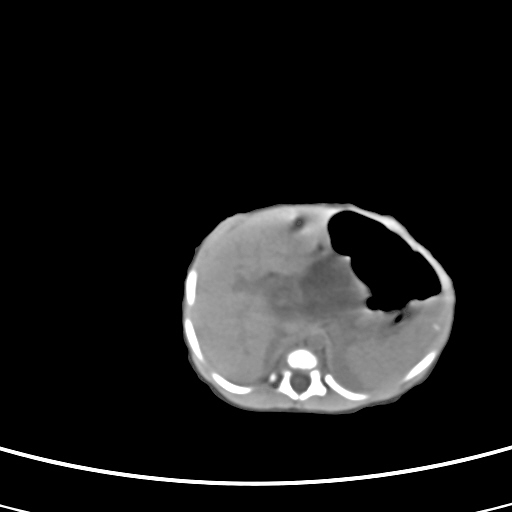

患儿,男性,出生后2天,在胎儿时b超已发现病变,患儿一般情况可。因病变部位偏向于右侧肾上腺区,目前考虑为神经母细胞瘤,不知各位能否支持。

反对定位在右肾上腺区的说法,那么神经母细胞瘤也可以暂时不予考虑。请看下图:

下面这幅图中,似乎可以见到肿瘤的薄包膜,其后与右肾之间的又是什么东西呢?这关系到肿瘤的定位、定性。我考虑病灶是位于肝十二指肠韧带内的畸胎瘤可能性比较大。请各位老师仔细看一下:

病灶巨大,位于右侧肾上腺区,与周围组织分界欠清,内见不规则钙化影,无明显脂肪组织,首先考虑神经母细胞瘤,但畸胎瘤不能排除。

手术结果为畸胎瘤